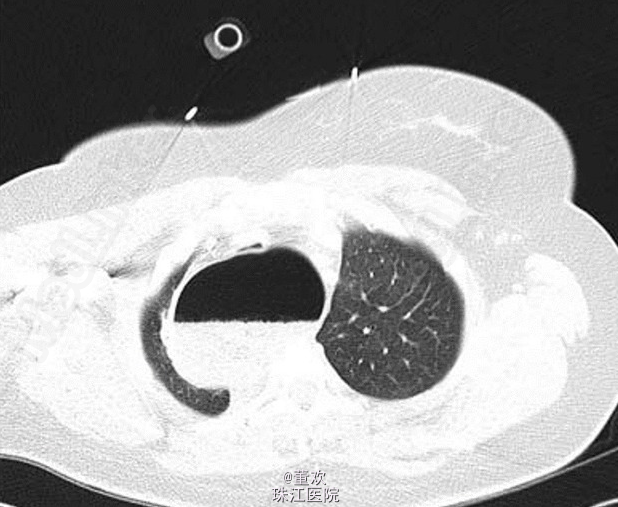

查体:双肺呼吸音较弱,右侧明显,无哮鸣音,未问及干湿性啰音。叩诊音未见明显异常。 辅助检查:胸片示右上肺透亮影;肺部 CT 示食管内有大量食物,呈显著扩张状态;严重压迫气管及气管内插管。具体图像如下。

诊断:巨食管症致呼吸暂停。 处理:给予放置鼻胃管,引流出大量胃内容物。拔管后行胃十二指肠镜检查,未发现存在梗阻。患者诊断为巨食管症,后转入一家三级医院行肌层切开术治疗。